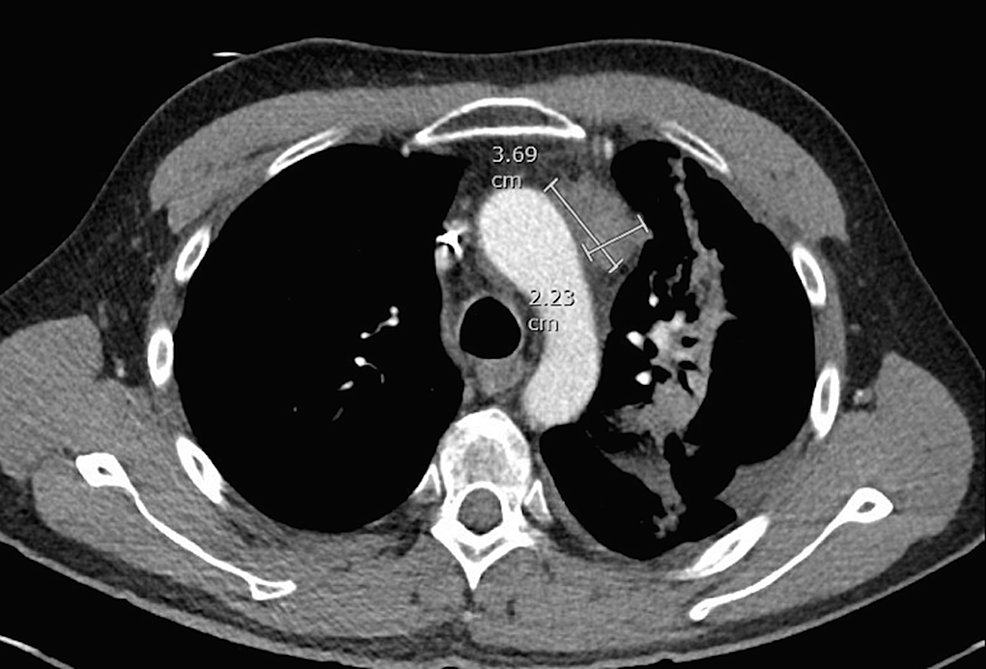

A 46-year-old male with stage IVB nodular sclerosis Hodgkin lymphoma received treatment with six cycles of ABVD (doxorubicin, bleomycin, vinblastine, dacarbazine) and then autologous stem cell transplant. Despite these treatments, he had progression of his disease. The positron emission tomography (PET) showed hypermetabolic activity in the anterior mediastinal mass and left hilar lymph node. He underwent radiation to the mediastinum. A subsequent computed tomography (CT) scan of the chest and liver showed a progression of the anterior mediastinal mass measuring 3.7 x 2.2 cm and a new mass in the left lobe of the liver measuring 2.9 x 2.8 cm (Figures 1-2).